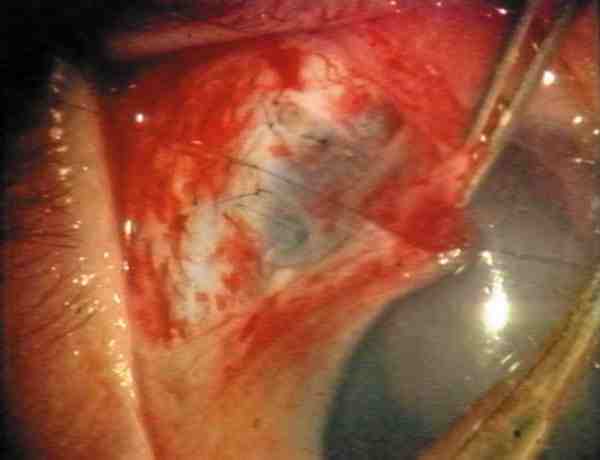

9. Trabeculectomía: Excisión del bloque interno de esclera-córnea-trabeculum. Recomendamos una sección de 2 ´ 2 mm de tejido (figura 2). Primeramente se perfila el lugar deseado, que debe comenzar en córnea y extenderse hasta la unión esclero-limbar (figura 3). La penetración en cámara anterior se realiza lentamente en una de las esquinas del cuadrado con el cuchillete quirúrgico. Se finaliza con tijera de Vannas (figura 4). La cámara anterior puede mantenerse con aire mientras se concluye el procedimiento.

08-04.jpg (12024 bytes)

Figura 4. Trabeculectomía con cuchillete y tijera de Vannas.